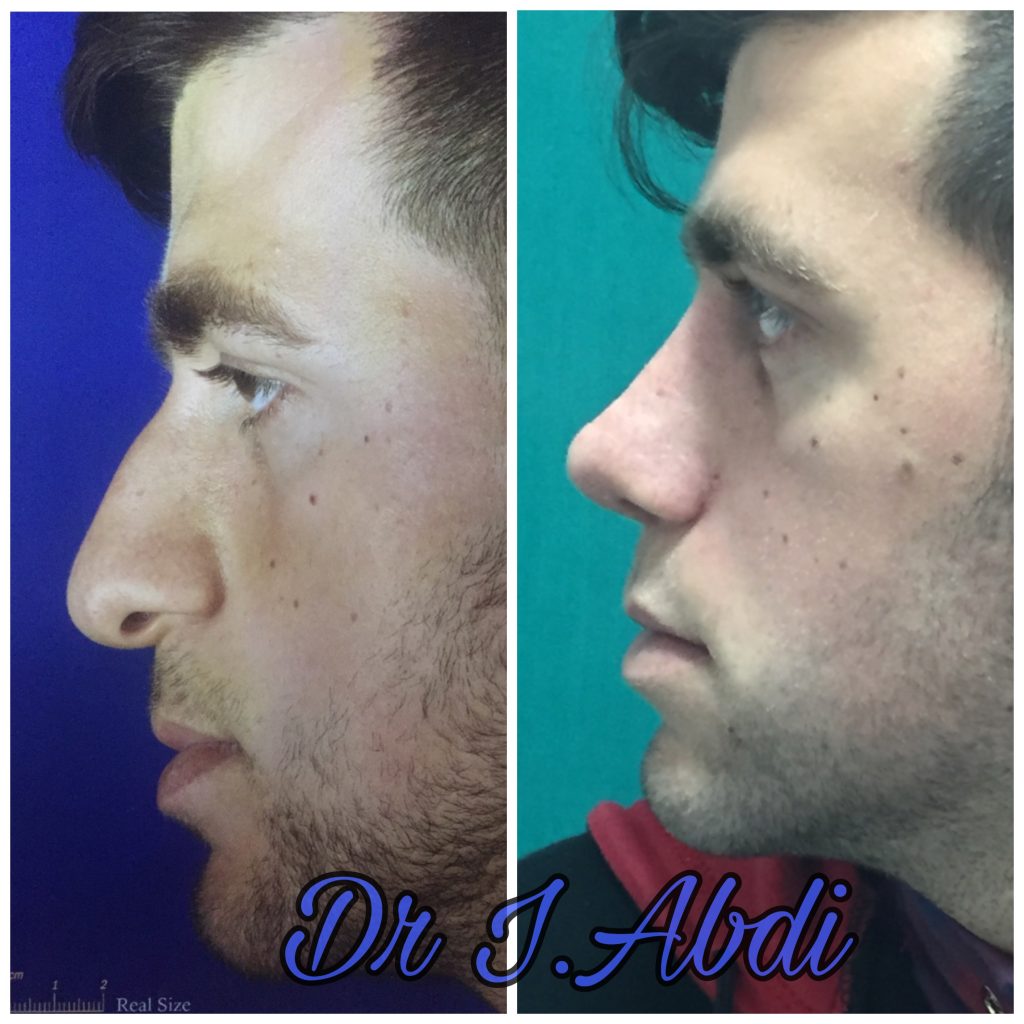

دکتر عیسی عبدی در رشت

دکتر عیسی عبدی در رشت

– متخصص جراحی فک , پلاستیک صورت و بینی

دکتر عیسی عبدی در رشت

جراحی فک , پلاستیک , صورت وبینی